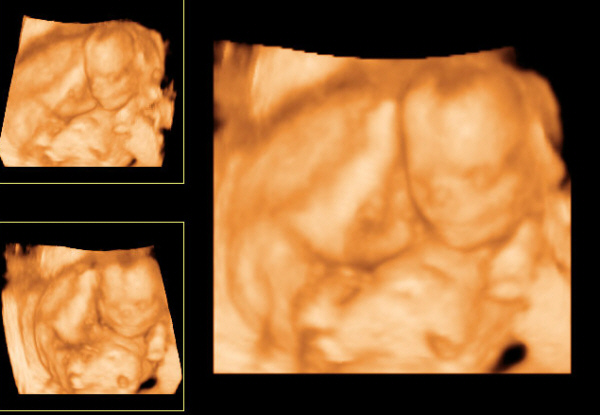

Csak gyorsan beköszönni jöttem.... Köszönjük a drukkokat, FIAM lesz, ez már 100000%. Boti szépen terpesztett, mutatta a fütyit, és a zacsirész is látszott, a golyók még nem látszanak, de a zacsi már megvolt, a fütyi meg szépen ágaskodott.... Imádom.

Méretekre pontosan 16+6 nak felel meg, így 1 nap a különbség csak, ez tökéletes a nő szerint. Kb. 20cm lehet már a kis manóseggű, és 17,5dkg. :D

Egy kép a szerelmemről:D

A Fütyink alulról nézve :D

Kép

Botikám, szerelmem :D